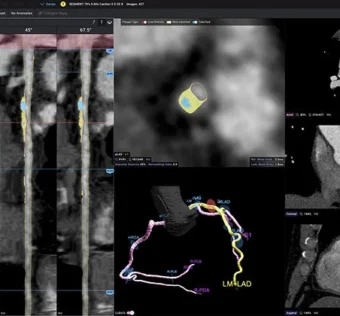

npj Digital Medicine - (Wednesday September 24, 2025) Hospital readmission is a key quality metric, yet post-discharge interventions often yield variable results. In the first large-scale randomized evaluation of causal machine learning in a health system, we assessed whether a novel model… ![]() Cigna to Cover Cleerly’s AI-Based Plaque Analysis, Expanding Access to Cardiovascular Imaging

HIT Consultant - (Wednesday September 24, 2025) What You Should Know: – Cleerly, a leader in AI-based cardiovascular imaging, has announced that Cigna will begin covering its Cleerly LABS Advanced Plaque Analysis starting on October 1, 2025. – The decision makes Cigna the… |